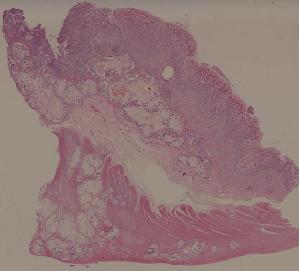

61. Gastric adenocarcinoma(Mucinous adenocarcinoma of the stamoch)